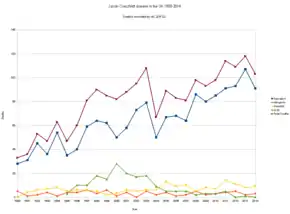

Treatment for vCJD involves supportive care.[5] As of 1990, 178 cases of vCJD have been recorded in the United Kingdom,[10] due to a 1990s outbreak, and 50 cases in the rest of the world.[7] The disease has become less common since 2000.[7] The typical age of onset is less than 30 years old.[3] It was first identified in 1996 by the National CJD Surveillance Unit in Edinburgh, Scotland.[7]